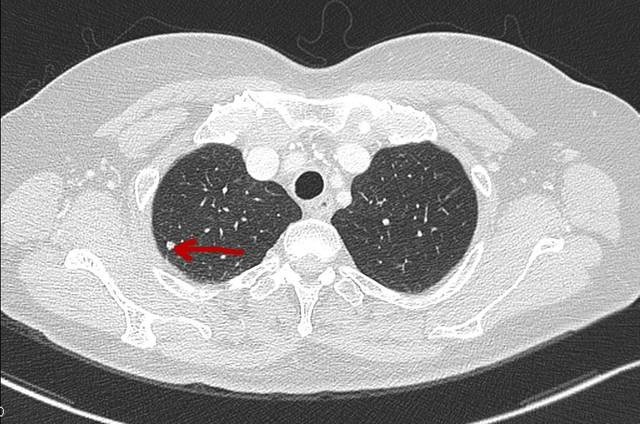

近年来医生,尤其是心胸外科医生,会有同样的一种感受,即临床医学发现越来越多的患者患有肺部小结节,有些是纯毛玻璃样结节,有些是实性结节,有些是部分实性结节等。

事实上,肺部小结节通常会被发现。医生通常根据自己的情况为患者制定3、6、12、24个月的随访时间。如果大多数结节在2年内没有观察到显著的生长发育,一般可视为良性或低度恶性。对于低风险群体:超过8mm:3、6、9、24月,进行增强CT、PET或穿刺检查。